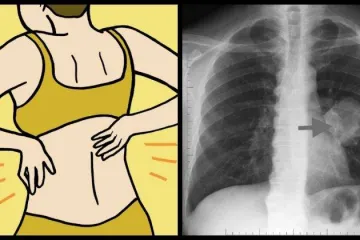

Այս մեքենան 11 տարի գտնվել էր գետի հատակում. տեսեք, թե ինչ հատնաբերեցին դրա ներս... Շաբաթվա օրը, երբ ծնվել եք՝ շատ բան կպատմի Ձեր բնավորության մասին Ինքնասպան խոյեր, հանցագործ առյուծներ, հոգեկան հիվնադ ձկներ. տարբեր կենդանակերպի ... Անհատական թեստ. ինչպես եք դուք բռնում բաժակը Հորոսկոպի ամենատականք նշանները Ալադիներ պատրաստելու ամենահաջողված բաղադրատոմսը, այժմ պատրաստում եմ միայն այս բա... Ջուսը նոր, սկանդալային ֆոտոսեսիա է ներկայացրել. ԼՈՒՍԱՆԿԱՐՆԵՐ Ծնողները շոկի մեջ էին՝ իմանալով, որ իրենց 14-ամյա դուստրը սեփական տուն է գնել. ա... Հորոսկոպի 5 գլխավոր լացկանները Կենդանակերպի 5 ամենապատասխանատու նշանները, ովքեր առողջ որոշումներ են կայացնում ո... Ջրհոս. Ձեզ սպասում են բազմաթիվ գայթակղություններ. Հունիսի 12 աստղագուշակ Կենդանակերպի ամենաերջանիկ նշանները 2019 թվականին Ամենալավ բնական լուծողականը, որը կմաքրի աղիները և կազատի փորկապությունից Այս մարդուն ընտանիքի անդամները 17 տարի պահել էին նկուղում կապված: Գիտե՞ք ինչն էր... Գոհար Ավետիսյանի ամուսինն առաջին անգամ խոսում է իրենց ամուսնալուծության մասին Իսկ դուք գիտեի՞ք թե ինչու են մահացած մարդկանց 2 մետր խորությամբ հուղարկավորում Օգտակար համարվող սննդամթերքի տեսակներ, որոնք իրականում կարող են վնասակար լինել Հորոսկոպի այս նշանները վերջապես կամուսնանան այս տարի. իսկ դու կա՞ս այս ցանկում 5 պատճառ, թե ինչու են գեղեցիկ աղջիկները ձախողվում սիրային հարաբերություններում Էդգար Իգիթյանը՝ առաջնեկին սպասելու լուրերի մասին Կնոջը դուր էր գալիս իր դստեր անունը. 2 տարի անց, կարդալով այն հակառակ կողմից, ան... Հունիսի 12-ի ձեր ռոմանտիկ հորոսկոպը Իմաստուններն հավատում են, որ աչքերը՝ հոգու հայելին են։ Ստուգեք այդպե՞ս է արդյոք։ Աշխարհում միակը համարվող այս գնացքի մեկ տոմսն արժեք 10 հազար դոլար․ երբ տեսնեք դ... Այս կարմիր մեքենայի մեջ հայրը բռնացրեց դստերը այն տղայի գրկում, որի հետ ինքն արգ... Եվ սա մայր է կոչվում. Մայրը չէր գալիս հիվանդանոց` հիվանդ որդուն տեսակցության 18 բան, որ անմիջապես կհիասթափեցնեն ցանկացած տղամարդու, անգամ, եթե դուք շատ գայթա... Պատահական կադր. Լիլիթ Հովհաննիսյանին գաղտնի նկարել են, երբ նա զբաղված էր ... Թոքերի քաղցկեղի 8 նշան, որ յուրաքանչյուր կին պետք է իմանա Այս աղջիկը 18 տարեկան է, ու պետք է տեսնել, թե ինչ տորթ նվիրեց նրան մայրը ծննդյան... 10 տղամարդուց 9-ը վախենում են այս բաներից. սակայն երբեք դա չեն խոստովանում Ինչպես են քաղաքացիները վերաբերում մինչամուսնական կապին. Հարցում Երեւանում. տեսան... Հունիսի 12-ի աստղագուշակ Թեստ, որը կօգնի բացահայտել ձեր թուլությունը Ինչպես կմահանա աշխարհը. հայտնի է մարդկությանը սպառնացող հիմնական վտանգը Ողջ բժշկությունը շոկի մեջ է. միայն տեսնեք, թե ինչ է իր ձեռքի մեջ ամուր բռնած եղե... Դիմացից նայելիս սա սովորական տուն է հիշեցնում, բայց միայն տեսեք, թե իրականում ին... 5 հայտնիներ, ովքեր նման են տիկնիկի. Առաջին տեղում Լիլի Մորտոն չէ Փոքրիկ Արփիի զվարճալի արկածները՝ առանձնատան բակում Երբ տեսնեք, թե ով է զբաղվում եղնիկի որսով, կցնցվեք. ո՞ւր է գլորվում աշխարհը Թեստ. Ընտրեք վարդը և մենք կպատմենք ձեր մասին, այնքան բան, որ դուք հաստատ չէիք սպ... Կնոջը դուր էր գալիս իր դստեր անունը. 2 տարի անց, կարդալով այն հակառակ կողմից, ան... Ինչպես կարելի է հասակ առնել («բոյ քաշել») Տարիներ առաջ 18 կգ կշռող այս աղջիկը լիովին վերականգնվել է և արդեն երկու երեխա ու... Ցնցված է դահլիճը, հեռուստադիտողը, միայն տեսնենք ինչ է կատարվել «Ամենախելացին» հա... Ուշադիր եղեք. եթե ապուր եփելիս մեծ քանակով փրփուր է առաջանում, ապա… Միայն տեսեք, թե ինչ կատարվեց Սանկտ-Պետերբուրգի գլխավոր հրապարակում, երբ այնտեղ հ... Ի՞նչ է կատարվում Երևանի գիշերային ակումբներում WOW. 7 հայտնի նշաններ, որոնց բացատրությունը քչերին է հայտնի Առավոտյան քաղցած վիճակում սո՞ւրճ եք խմում. անպայման կարդացեք սա